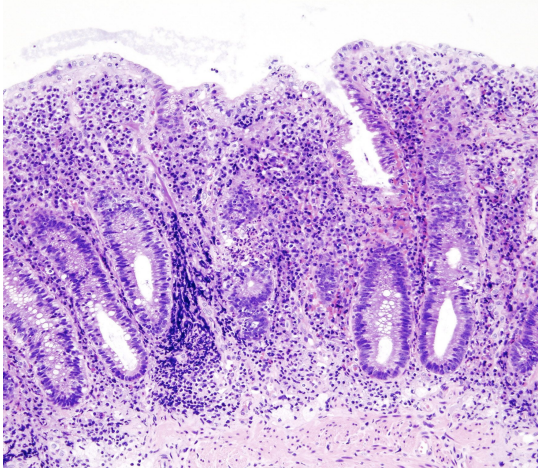

UC on histology will reveal _ and _

A

UC on histology will reveal crypt distortion and abscesses with neutrophils